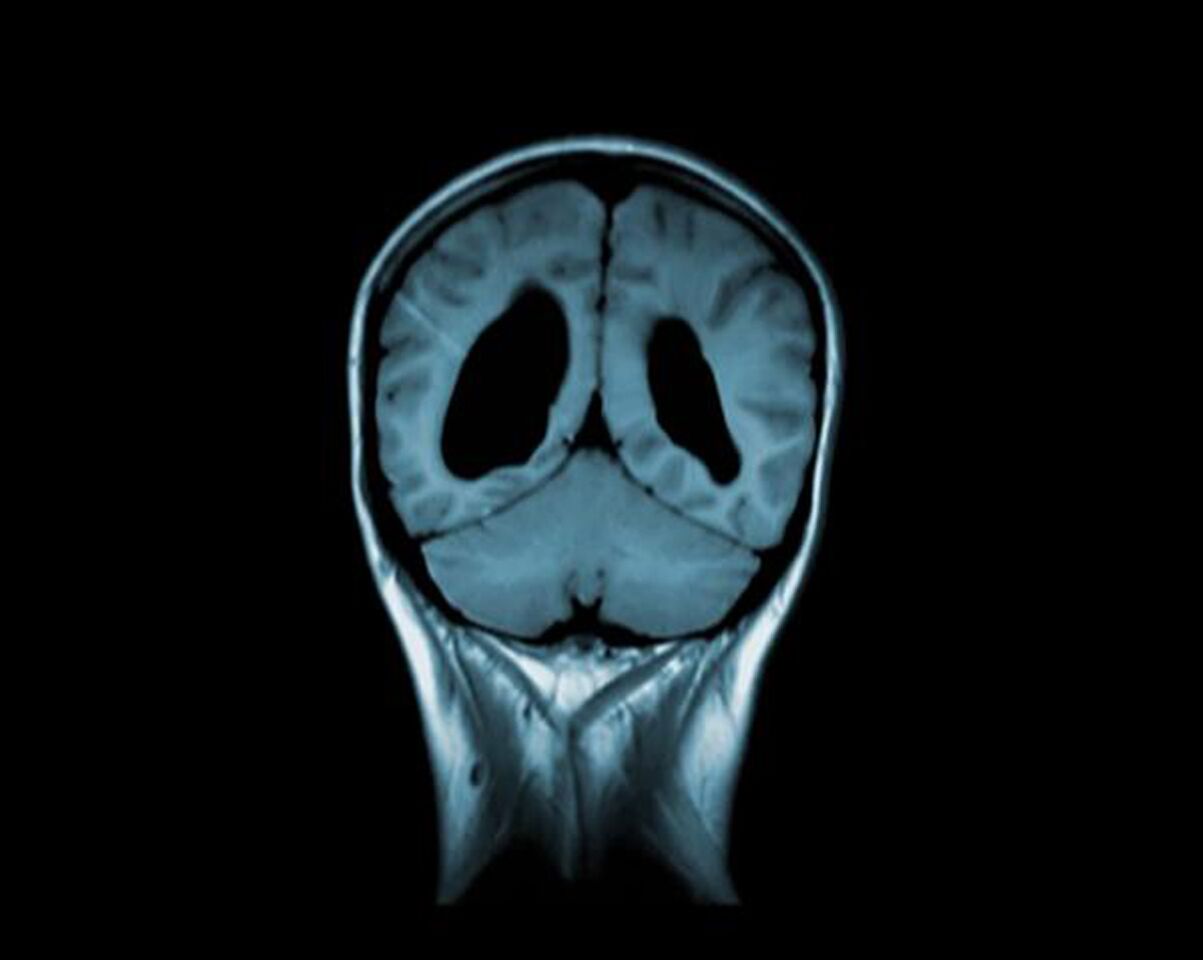

Florence Razoux / Art & Science: From the Brain to Body Fluids

Florence (Flo) Razoux is a biologist from background with a PhD in neurosciences & biomedical engineering. In parallel to their scientific career, Razoux started to explore an interdisciplinary creative landscape and has gradually become an active member of the Art & Science community. Bridging s...